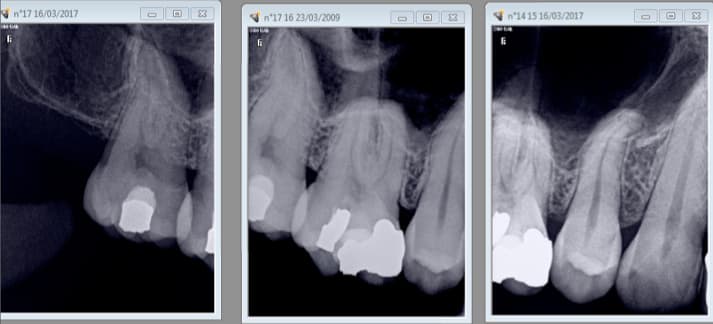

Celui ci bien complet.-)

Signe d'appel la petite souris est passée pour la 11. -)

Pourquoi elle , il y en a d'autres qui frétillaient de la queue ;o)